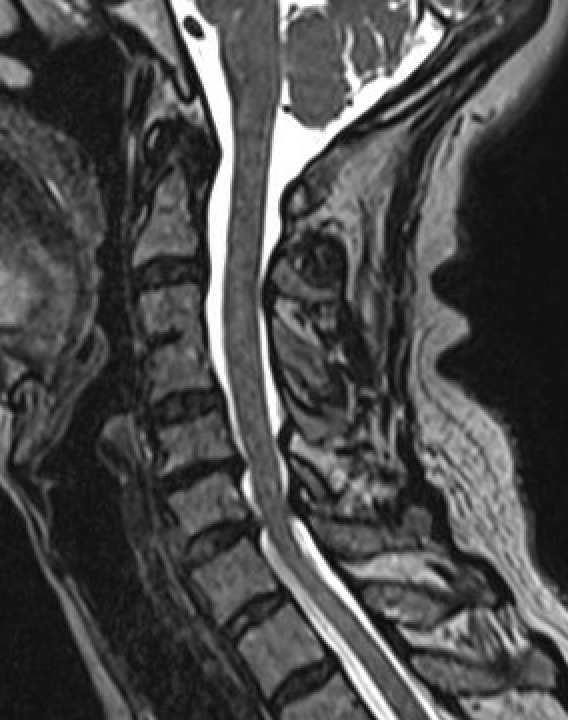

X-ray

Typical changes of spondylosis

- disc space narrowing

- osteophyte formation

- degenerative facet & uncovertebral joints

Severe C5/6 disc degeneration